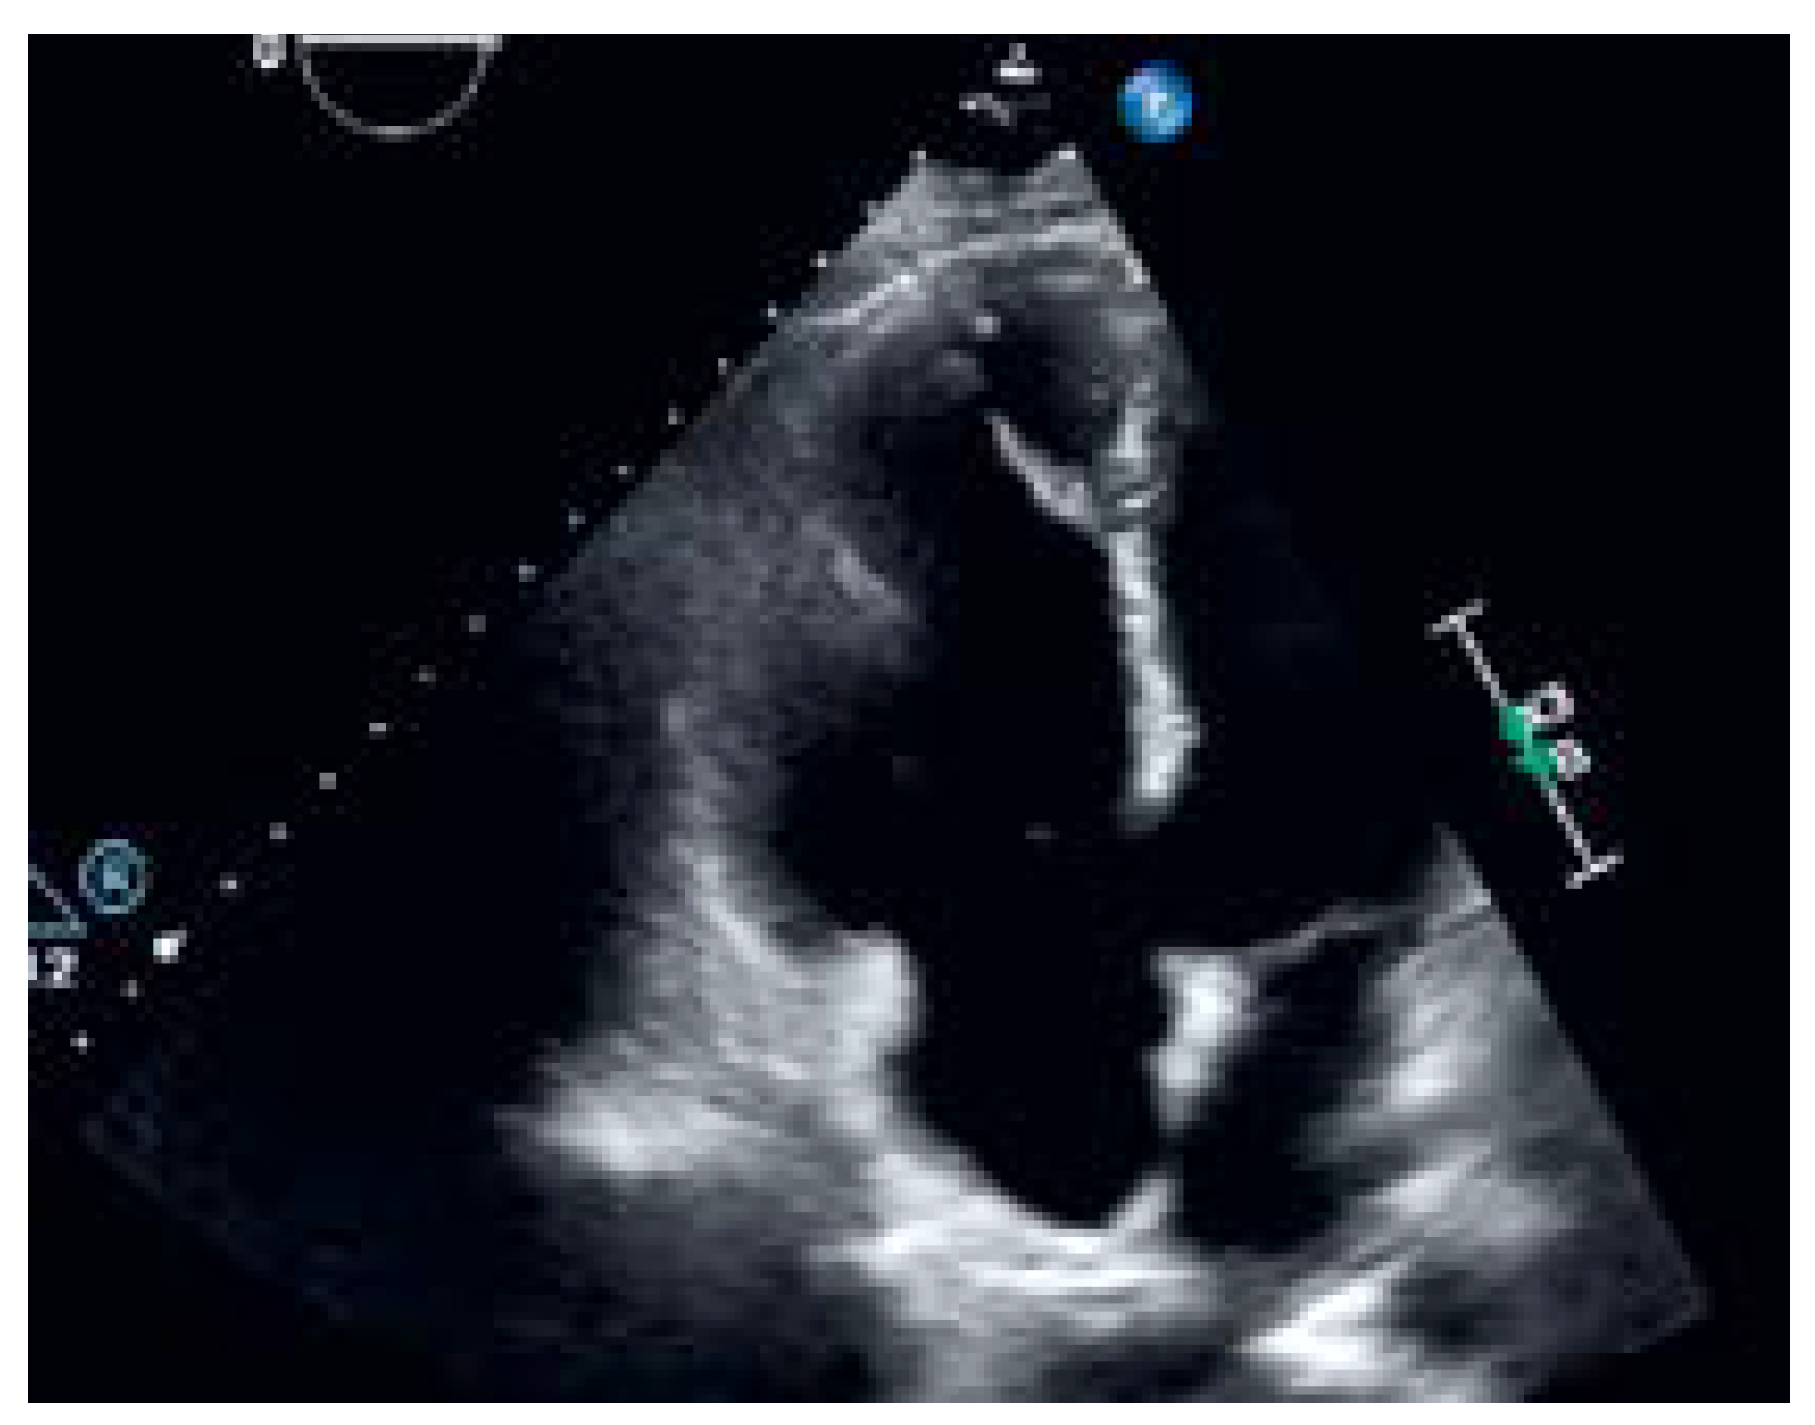

Sinus Venosus Atrial Septal Defect with Partial Anomalous Pulmonary Vein Return †

Case description